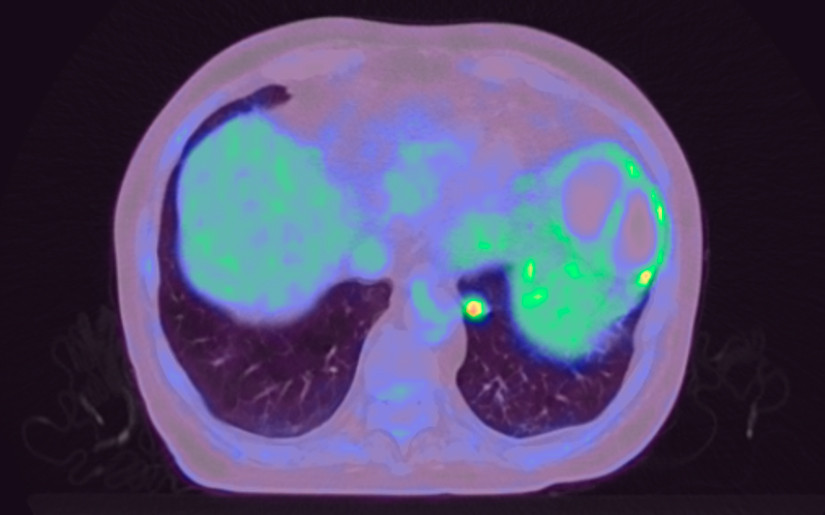

Pasienten utviklet i mellomtiden magesmerter og utspilt buk. Grunnet respirasjonsbesvær ble han lagt på intensivpost med respirasjonsstøtte. Endoskopisk ultralydundersøkelse måtte utsettes, men man gjorde ny FDG-PET/CT fire år etter siste undersøkelse. Denne gangen var det økt FDG-opptak basalt i venstre underlappstumor (figur 3).